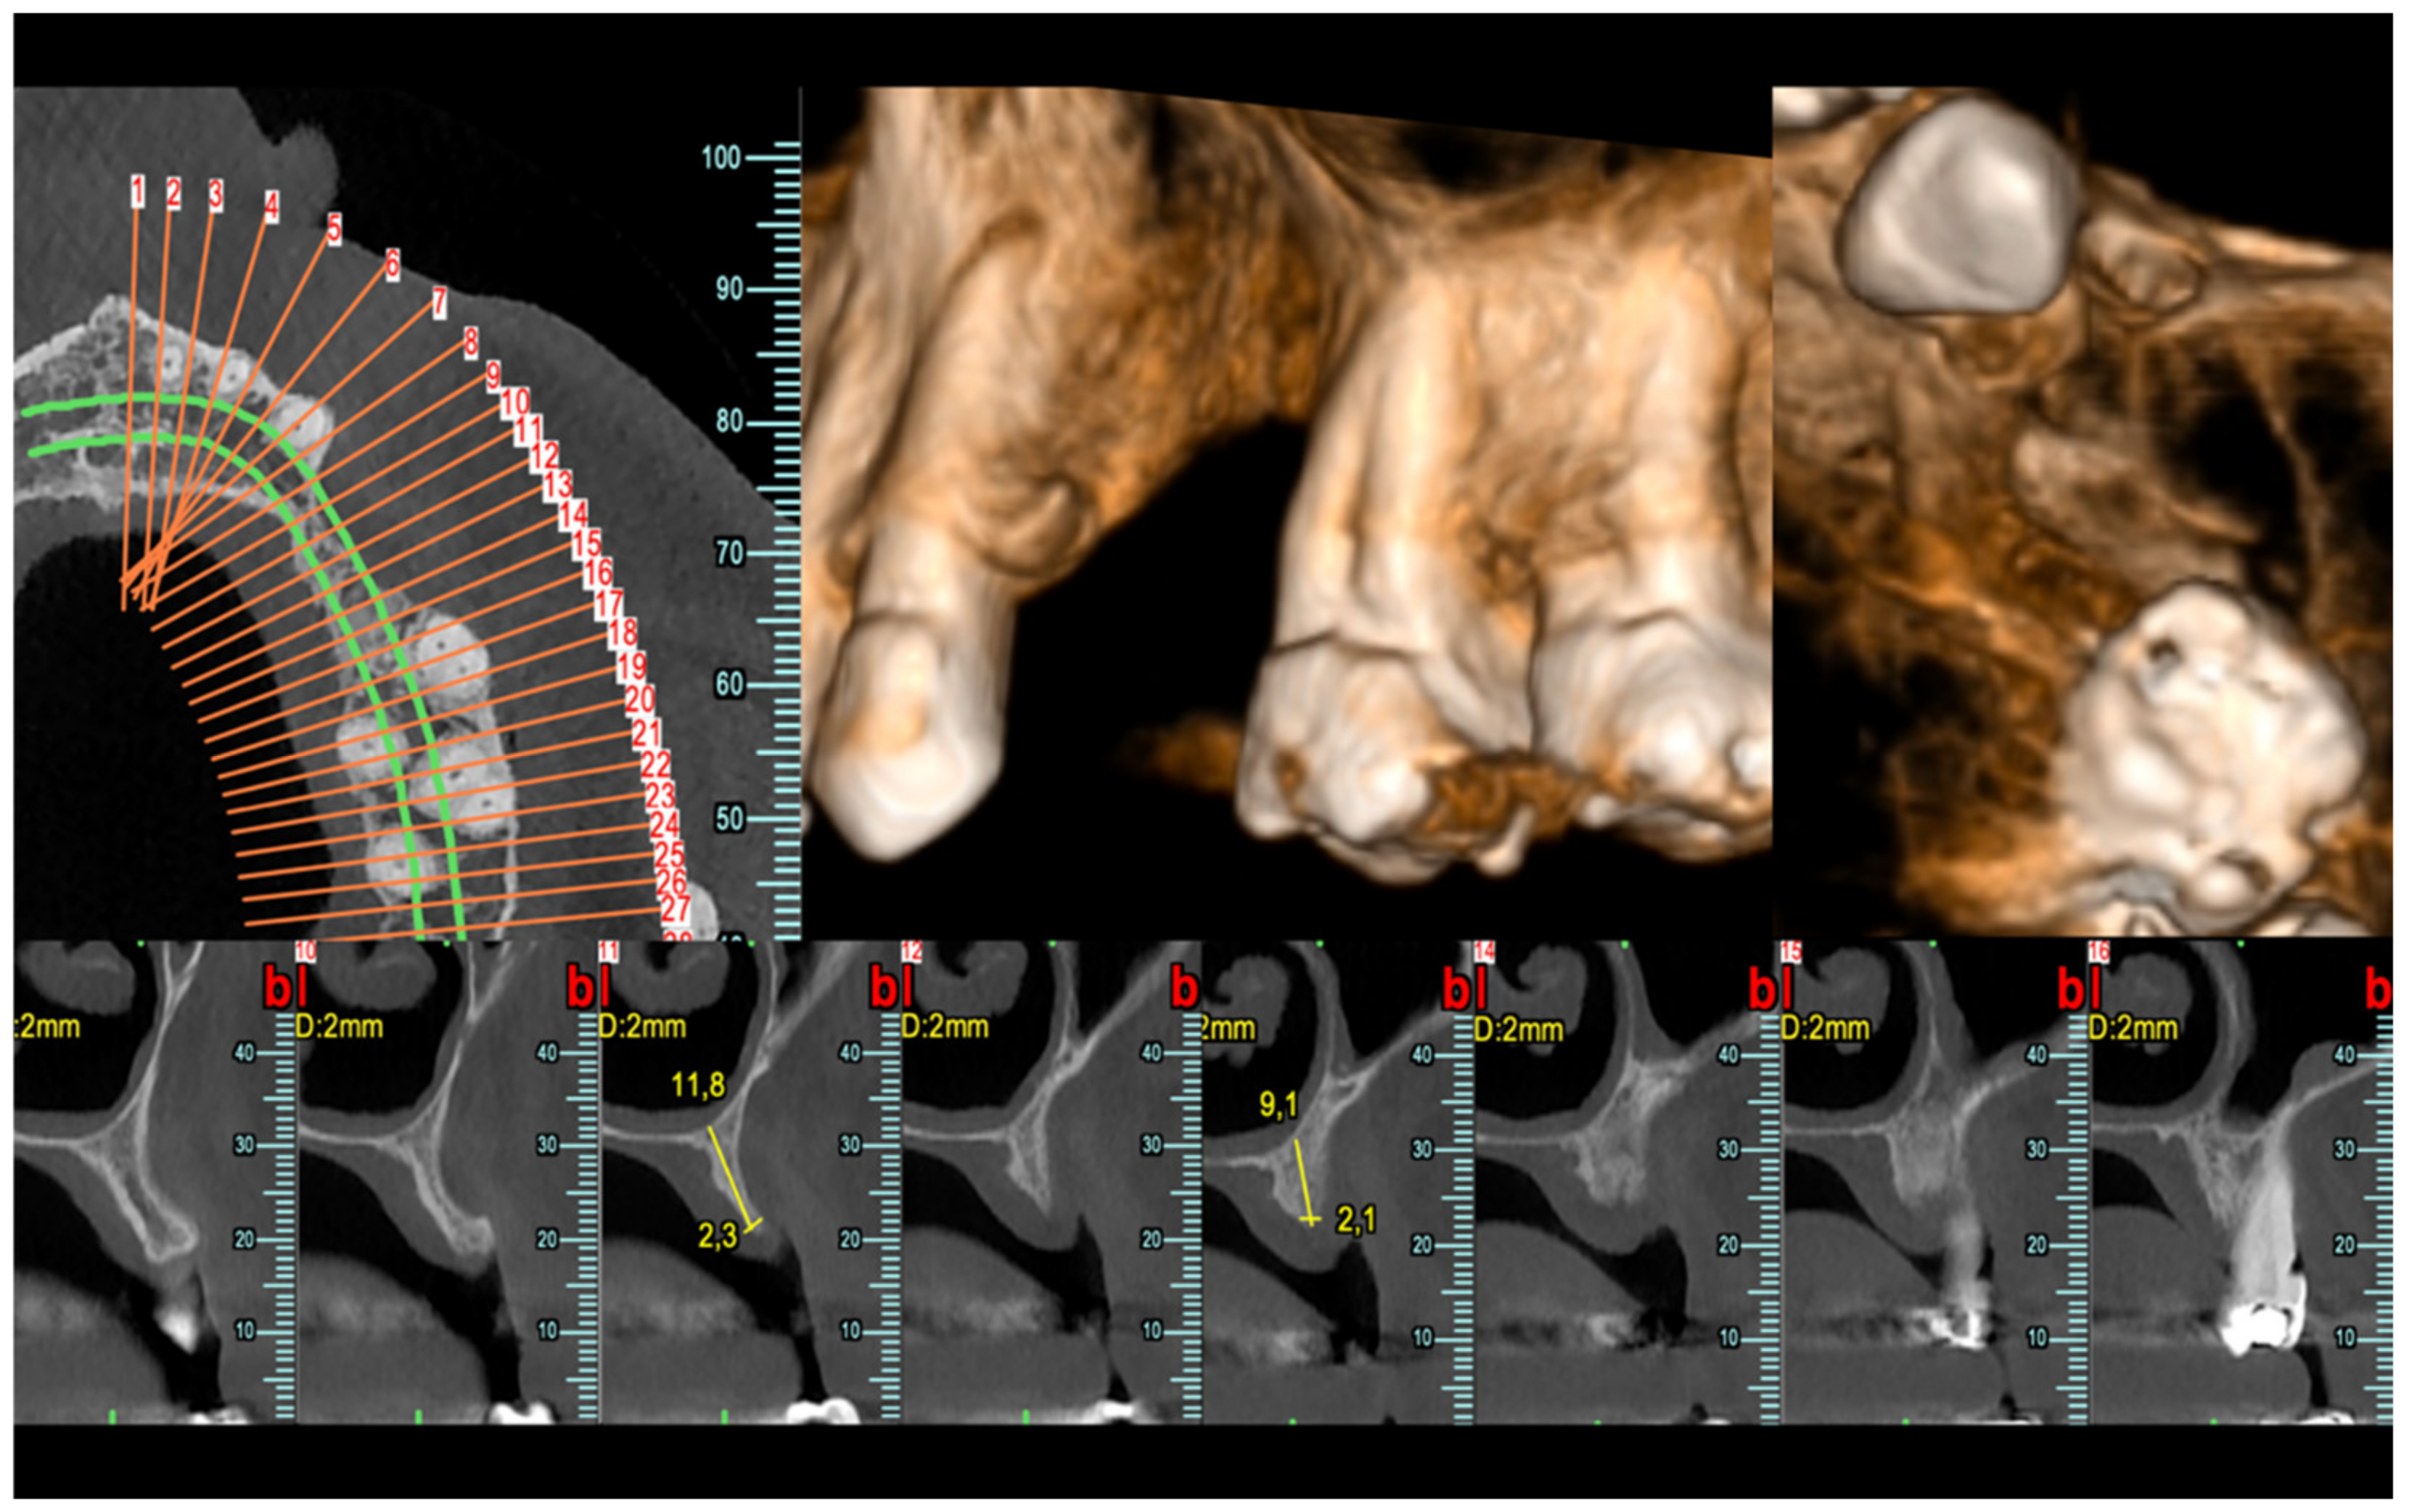

The patient was a 56-year-old male with history of periodontal disease, had lost 24–25 six years before consultation and at the time was looking to replace both. His teeth had migrated in the meantime and tooth 26 had a 9 mm pocket probing depth (PPD) on its mesial aspect. The shift of the molars closed the interproximal space; therefore, the treatment plan for the area was the horizontal augmentation of the edentulous space and an attempt to regenerate as much attachment as possible at the mesial of 26. The plan after that would be to place a single implant at the site of 24 to avoid a tooth of incongruous size. CBCT (Figure 1) shows the local anatomy at baseline.

Figure 1.

CBCT showing the severely resorbed area of 24–25 and the advanced bone loss at the mesial aspect of 26.